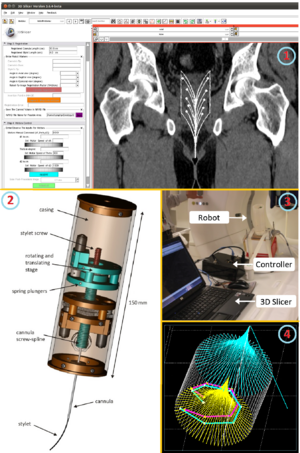

- 3.40 Openigtlink Interface for State Control and Visualisation of a Robot for Image-Guided Therapy Systems

- 4.16 Compact Robotically Steerable Image-Guided Instrument for Multi-Adjacent-Point (MAP) Targeting